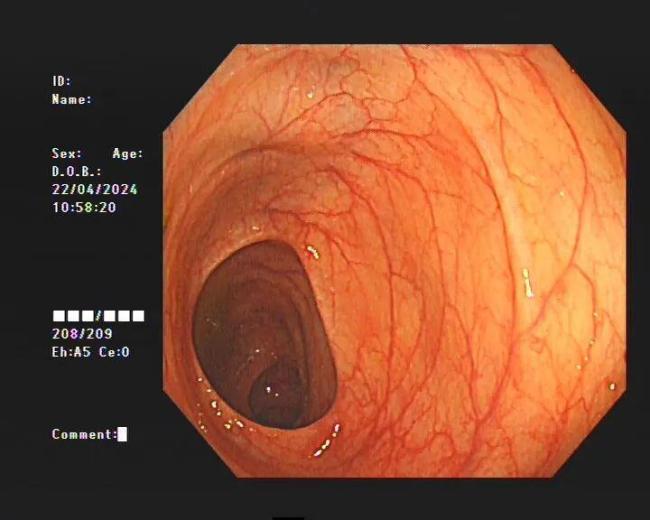

直到2024年4月中旬,季女士发现所有的通便茶都不管用了,腹部持续胀痛,才到医院就诊。检查结果显示,她的整条大肠内壁呈现出棕黑色蛇皮样,黑色素沉着明显,被诊断为“结肠黑变病”。若继续发展,有癌变的可能。经过治疗,季女士的便秘症状有了明显的好转。

临床上许多患者自行口服药物后筛查肠镜,均有不同程度的结肠黑变病。正常的结肠黏膜是淡红色的,看起来光滑平坦,黏膜表面的小血管纹理清晰可见。而结肠黑变病的肠黏膜色泽呈现棕色、褐色,有豹纹或者蛇皮一样的条状纹,严重的甚至会变成黑色。